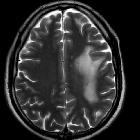

Tumefactive demyelinating lesion (TDL), also sometimes referred to as monofocal acute inflammatory demyelination (MAID), is a locally aggressive form of demyelination, usually manifesting as a solitary lesion (or sometimes a couple of lesions) greater than 2 cm that may mimic a neoplasm on imaging.

On imaging, they usually present with relatively little mass effect or surrounding edema, contrast enhancement in an open-ring pattern, high ADC values, and low relative cerebral blood volume (rCBV).

Tumefactive demyelinating lesions tend to be large but with relatively little mass effect or surrounding edema. Centrally located dilated veins have also been observed within these lesions .